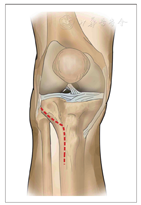

为此我们研发了一种符合胫骨后外侧平台解剖形态的旋转支撑接骨板(图1),可经前外侧入路[6](图2),经上胫腓关节间隙前方旋转环绕至胫骨平台后外侧,进行骨折块的复位和支撑固定,术中无需显露膝关节后方或后外侧即可置入和固定。这种骨膜下操作可有效避免神经、血管损伤。前期的生物力学研究和有限元分析证明此旋转支撑接骨板的固定效果可靠,能够满足临床要求[7]。自2016年5月起,我们采用此种手术方式治疗胫骨后外侧平台骨折,本研究对随访1年以上的病例进行回顾性分析,目的是:①介绍经前外侧入路使用旋转支撑接骨板治疗胫骨后外侧平台骨折的手术方式和手术技巧;②评估该手术方式的临床疗效;③探讨该手术方式在胫骨后外侧平台骨折治疗中的优势。

旋转支撑接骨板由直板体部、弯曲颈部和稍宽大的头部构成,体部置于胫骨上外侧,颈部可经骨间膜孔处绕向后外方,头部像"手掌"托住后方骨折块。其适应证为:胫骨后外侧平台骨折块较小,难以通过外侧螺钉固定者及胫骨后外侧平台粉碎性骨折。